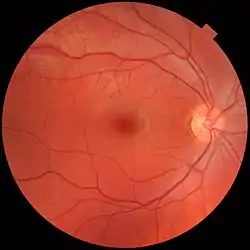

In adult humans, the entire retina is about 72% of a sphere about 22 mm in diameter. The entire retina contains about 7 million cones and 75 to 150 million rods. The optic disc, a part of the retina sometimes called "the blind spot" because it lacks photoreceptors, is located at the optic papilla, where the optic-nerve fibres leave the eye. It appears as an oval white area of 3 mm2. Temporal (in the direction of the temples) to this disc is the macula, at whose centre is the fovea, a pit that is responsible for sharp central vision, but is actually less sensitive to light because of its lack of rods. Human and non-human primates possess one fovea, as opposed to certain bird species, such as hawks, that are bifoviate, and dogs and cats, that possess no fovea, but a central band known as the visual streak. Around the fovea extends the central retina for about 6 mm and then the peripheral retina. The farthest edge of the retina is defined by the ora serrata. The distance from one ora to the other (or macula), the most sensitive area along the horizontal meridian, is about 32 mm.

Biometric identification and diagnosis of disease

The bifurcations and other physical characteristics of the inner retinal vascular network are known to vary among individuals,[47] and these individual variances have been used for biometric identification and for early detection of the onset of disease. The mapping of vascular bifurcations is one of the basic steps in biometric identification.[48] Results of such analyses of retinal blood vessel structure can be evaluated against the ground truth data[49] of vascular bifurcations of retinal fundus images that are obtained from the DRIVE dataset.[50] In addition, the classes of vessels of the DRIVE dataset have also been identified,[51] and an automated method for accurate extraction of these bifurcations is also available.[52] Changes in retinal blood circulation are seen with aging[53] and exposure to air pollution,[54] and may indicate cardiovascular diseases such as hypertension and atherosclerosis.[55][56][57] Determining the equivalent width of arterioles and venules near the optic disc is also a widely used technique to identify cardiovascular risks.[58]

A number of different instruments are available for the diagnosis of diseases and disorders affecting the retina. Ophthalmoscopy and fundus photography have long been used to examine the retina. Recently, adaptive optics has been used to image individual rods and cones in the living human retina, and a company based in Scotland has engineered technology that allows physicians to observe the complete retina without any discomfort to patients.[62]